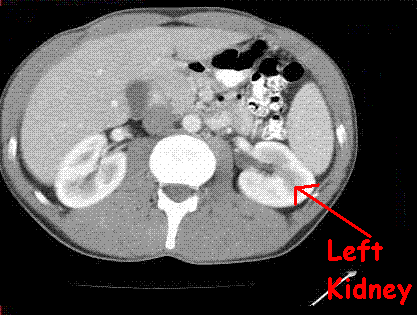

What structure is this?

This structure is the left kidney.

The left kidney starts around what vertebral body?

The left kidney usually starts around T12.